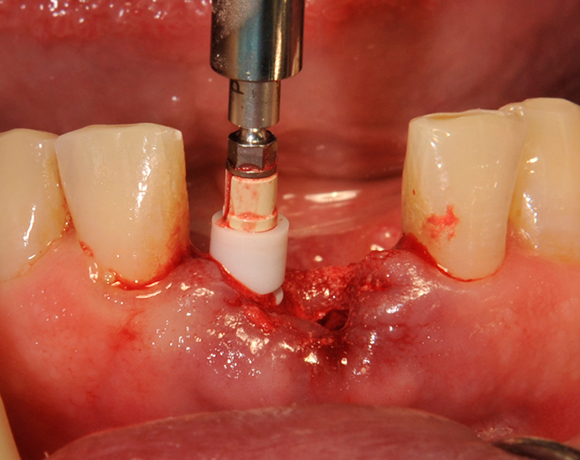

Die Keramikimplantate der Fa. Dentalpoint lassen sich auch zur Sofortimplantation verwenden. Das bedeutet, dass nach Extraktion nicht beherdeter Zähne direkt die Implantate gesetzt werden können.

Im vorliegenden Patientenfall wurden die beiden nicht erhaltungswürdigen, mittleren Unterkieferschneidezähne durch zwei Vollkeramikimlpantate ersetzt.